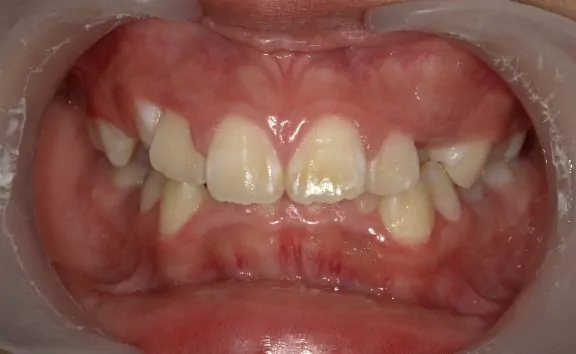

治療前

診断名・主な症状

八重歯・前歯のガタガタ

年齢

11歳女児